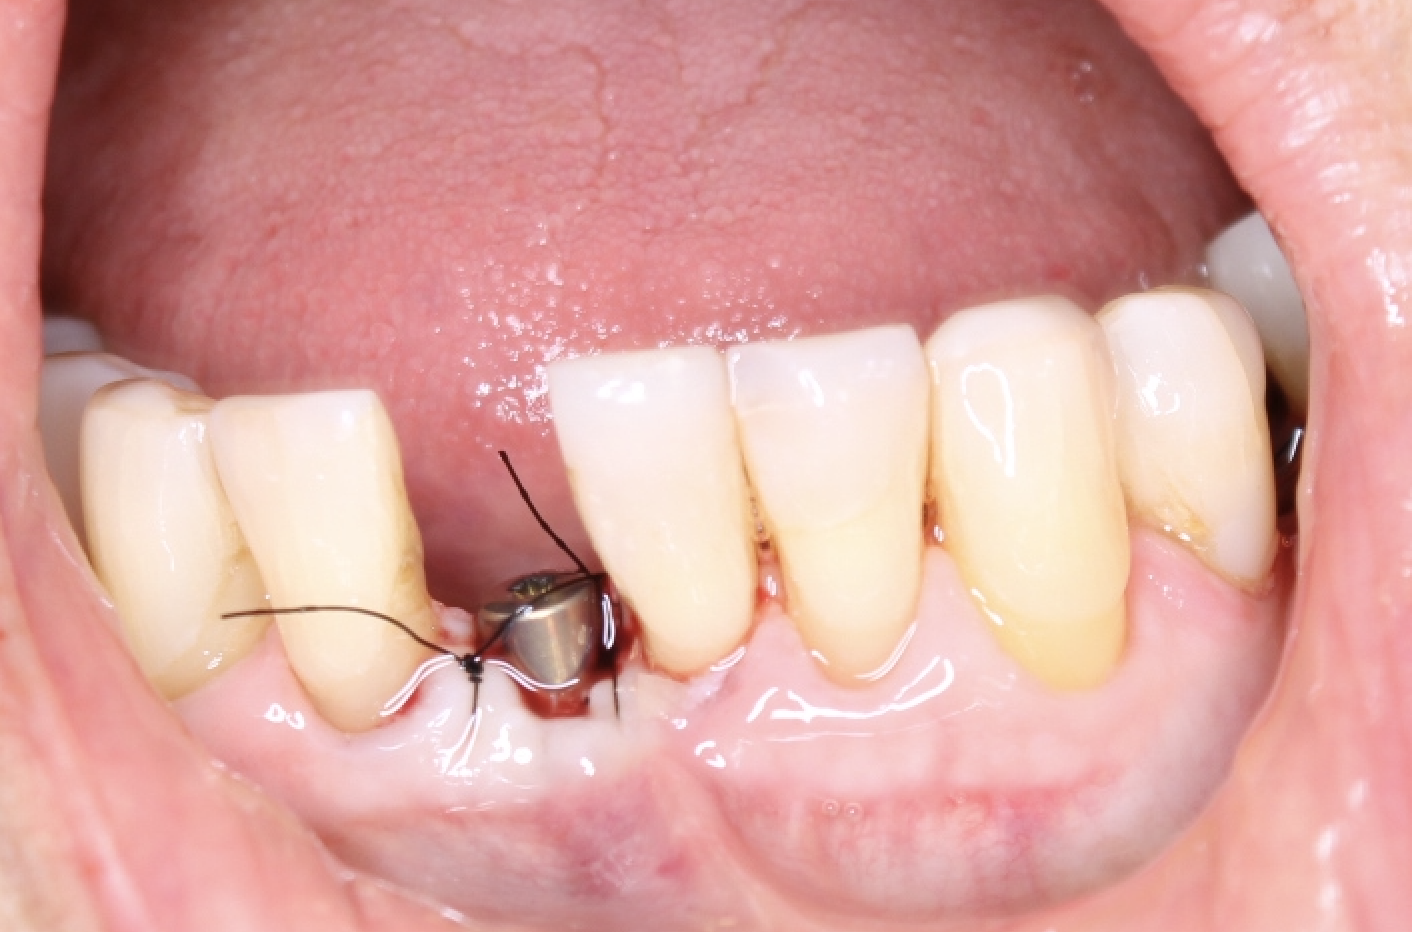

¿Sabías que la colocación de implantes dentales ya no es como antes? Gracias a los avances tecnológicos, este procedimiento es ahora más preciso, cómodo y seguro.

Olvídate de las intervenciones invasivas y las largas recuperaciones. En este caso clínico, te mostraremos cómo la tecnología digital se une a la experiencia de nuestros especialistas para lograr resultados sorprendentes.